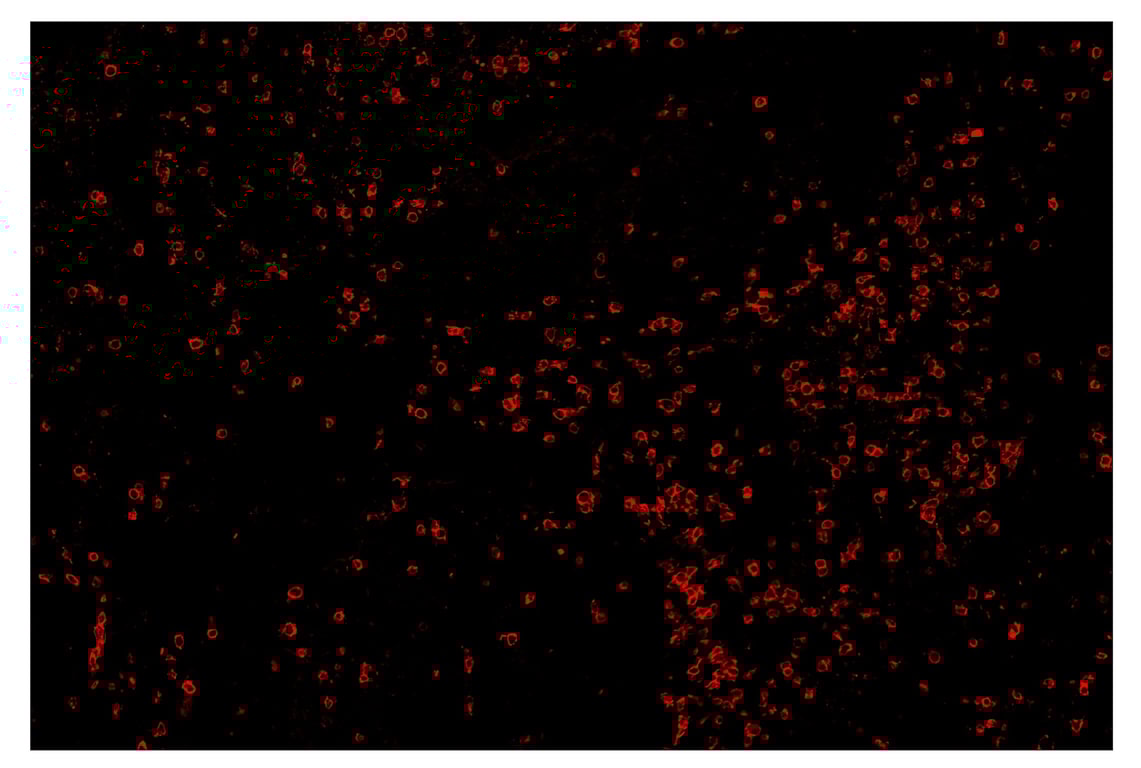

SignalStar™ multiplex immunohistochemical analysis of paraffin-embedded human colorectal adenocarcinoma using CD8α (D8A8Y) & CO-0004-594 SignalStar™ Oligo-Antibody Pair #19166 (yellow) and Granzyme B (D6E9W) & CO-0009-750 SignalStar™ Oligo-Antibody Pair #60358 (cyan). All fluorophores have been assigned a pseudocolor, as indicated. Staining was performed on the BOND RX by Leica Biosystems.

Immunohistochemistry Image 7: CD8 alpha (D8A8Y) & CO-0004-594 SignalStar<sup>™</sup> Oligo-Antibody Pair